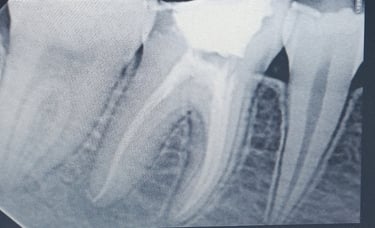

Root Canal Treatment (RCT)

A painless procedure to remove infection from inside the tooth, preserving your natural teeth and preventing further decay.